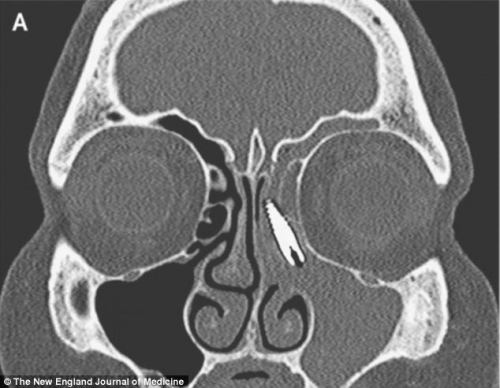

Medicii i-au făcut imediat o radiografie, iar ceea ce au văzut i-a lăsat fără cuvinte. Pensionara avea in nas un surub care ii fusese montat in maxilar in urmă cu multi ani.

Surubul de doi centimentri s-a deplasat insă de la locul initial si a ajuns in nas, ceea ce i-a provocat pacientei dureri de nedescris.